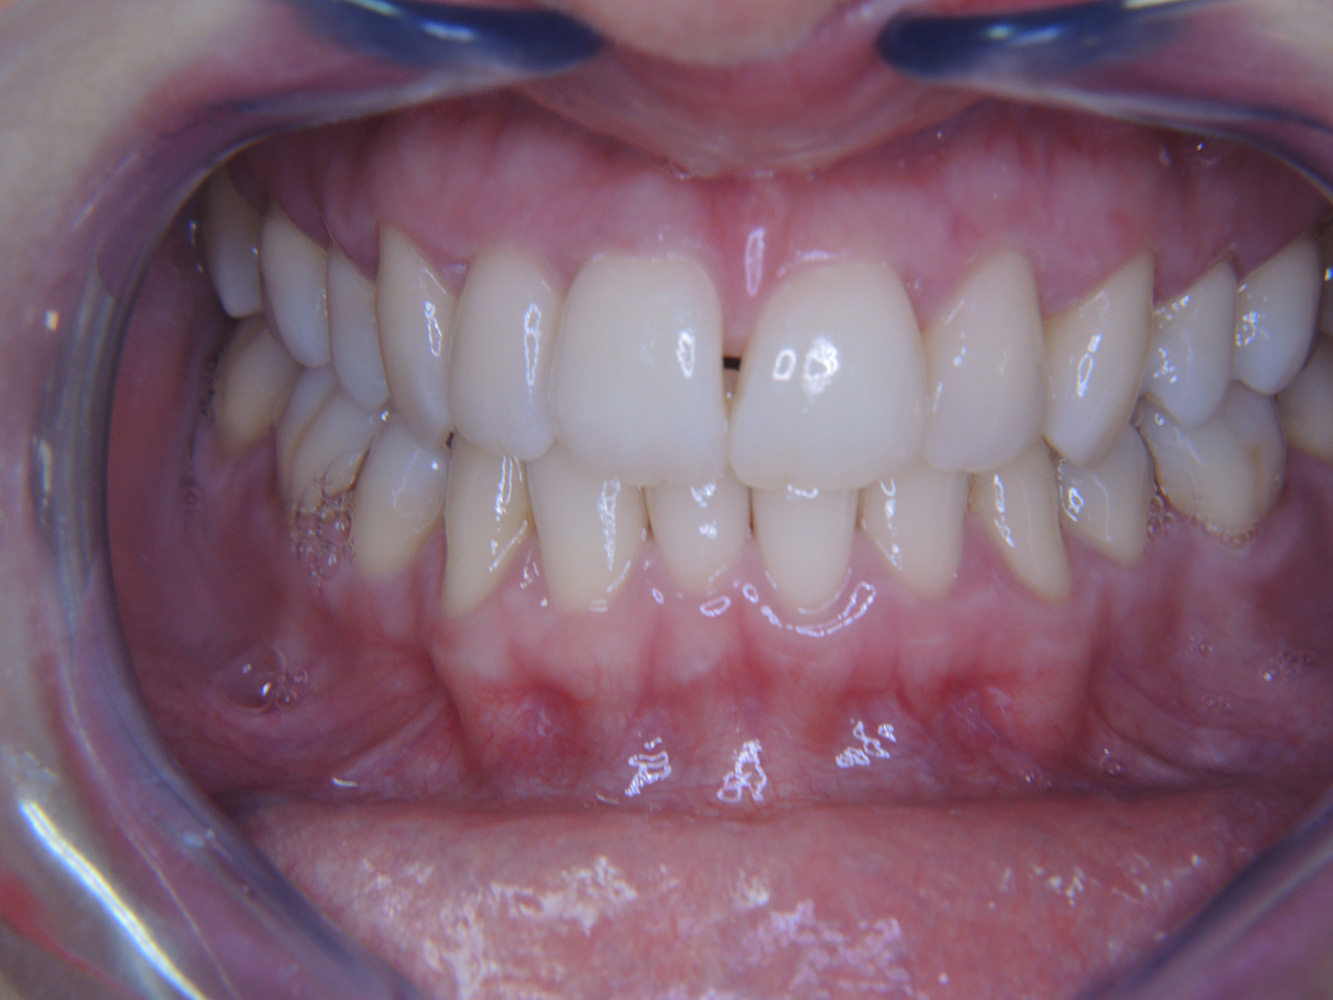

Case presentation: Complex Dental Prosthesis Management

The direct relationship between intraoral and general health, as well as the bidirectional influence that they may have on one another, is well-known (1,2). It is absolutely essential to consider both factors when planning preventive intraoral measures and treatment in the dental practice. The primary objective is the maintenance of patient health and quality of life from both dental and medical perspectives. more